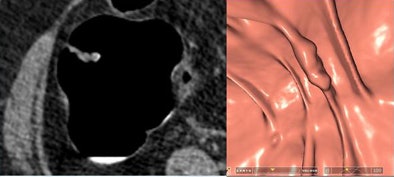

Two lesions were detected only by CAD and were not reported by the radiologists as flat due to low conspicuity. Two lesions with heights < 1 mm weren't seen at CTC but were detected at conventional colonoscopy.

| Two lesions showing a typical cigarlike appearance were detected only by CAD and were not reported by the radiologists as flat due to low conspicuity. Left to right: 2D image, 3D endoscopic view, colonoscopy view. |